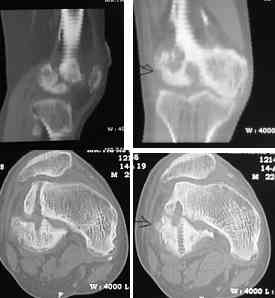

I opened it up from the lateral aspect.

Freed up the non-union site with minimal disturbance to the posterior and lateral soft tissue attachments on the lateral condyle fragment.

Applied a distractor between femoral shaft and tibia, to create a space on the lateral aspect.

This brought the lateral condylar fragment into a position that seemed to be reasonably well aligned, but showed up a bone gap.

This was fixed temporarily, bone grafted with tricortical struts, and fixed by two cancellous screws. The fragment was not large enough to afford any fixation to a plate or such implant, and the screws held it compressed well to the rest of the distal femur.

Post-op - limb is well aligned, rom 0-30, but I am not pushing that right now, for the next two or three weeks.

Further plan - hope that the screws hold the fragment appropriately till union, but if the stability on table is anything to judge by, that should not be a problem.

Quadricepsplasty after a year or so, to restore flexion.

Pictures attached.

Mangal Parihar